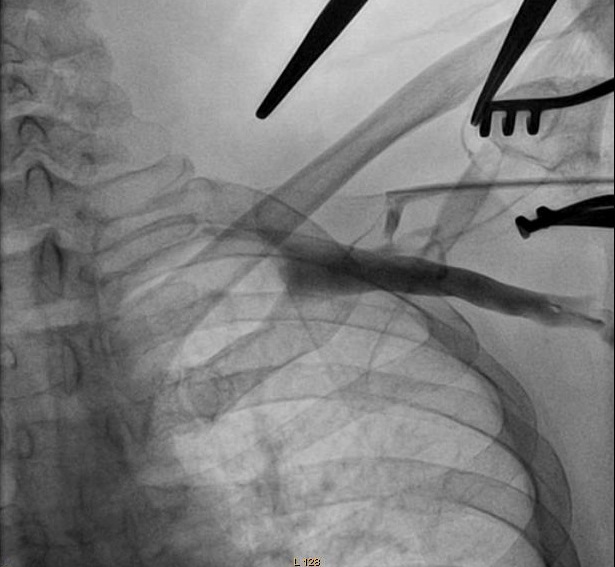

Axillary vein puncture

• Fluoro guided

• Junction of clavicle and first rib

• Walk along first rib

Venogram

• Difficult puncture

• Pre-existing leads

• 10-15 ml of contrast from ipsilateral arm

• Management of stenosis

Puncture with venogram